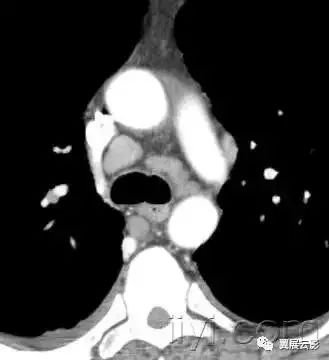

五、主肺动脉窗

解剖:纵膈的一部分,前界是升主动脉,后界是降主动脉,上界是主动脉弓,下界是左肺动脉,内侧为动脉韧带,外侧是胸膜和左肺。

平片和CT:正位胸片上,在主动脉弓以下,左肺动脉以上纵膈的弧形凹入。主动脉迂曲的时候,可以发生形状的改变。多种炎性病变和肿瘤性病变都可以导致主肺动脉窗的淋巴结增大。